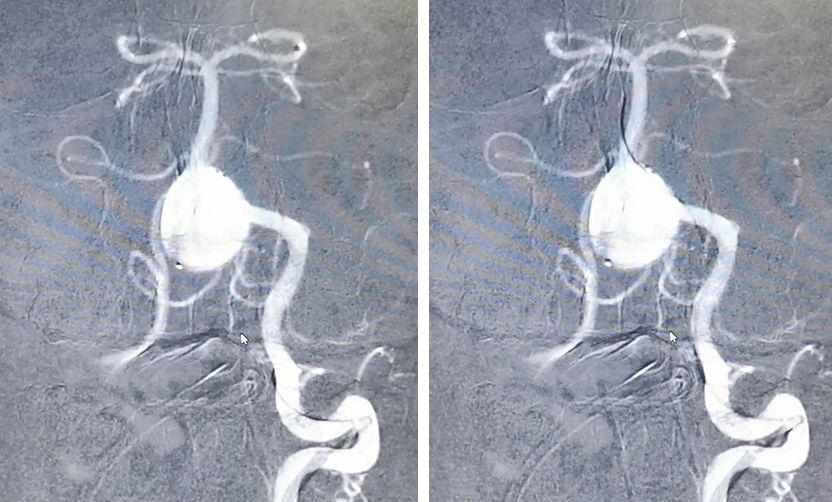

经右椎动脉逐步填塞大弹簧圈进入动脉瘤(Microplex-18系列),逐步将动脉瘤疏松填塞。期间微导管头端受到弹簧圈阻力,会缓慢回撤,此时不必刻意调整微导管再次深入动脉瘤腔内,因为我们最主要目的不是严密填塞动脉瘤—那是PED的任务—而是闭塞右侧椎动脉

最后,用小弹簧圈完全闭塞右侧椎动脉(PICA以远)

左椎动脉造影显示椎-基底动脉及远端血管通畅,动脉瘤虽然部分显影,但是PED最终会让动脉瘤完全修复。